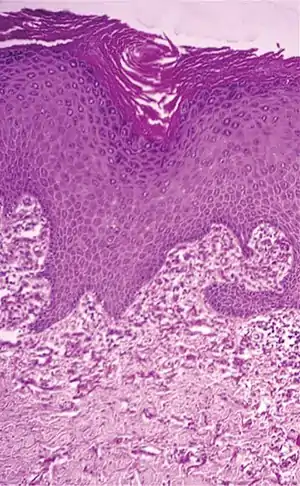

| Condition | Distinctive features | Histopathology |

|---|---|---|

| Actinic elastosis (most common, also called solar elastosis) |

Elastin replacing collagen fibers of the papillary dermis and reticular dermis | ![]() |

| Elastosis perforans serpiginosa | Degenerated elastic fibers and transepidermal perforating canals (arrow in image points at one of them)[8] | ![]() |

| Perforating calcific elastosis | Clumping of short elastic fibers in the dermis.[8] | ![]() |

| Linear focal elastosis | Accumulation of fragmented elastotic material within the papillary dermis and transcutaneous elimination of elastotic fibers.[8] | ![]() |